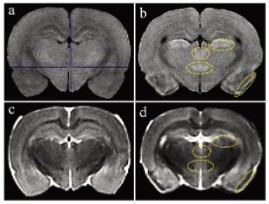

图1显示了T1和T2加权MRI图像。与对照组相比, 匹罗卡品处理的动物在梨状皮质、丘脑外侧核、丘脑室周后核和大脑下丘脑后核的T1加权图像显示出高T1信号(图1a和b)。在匹罗卡品处理的动物的T2加权图像中,与对照组相比,在梨状皮质观察到低T2信号,对应于高T1信号区(图1c和d)。其他3个高T1信号区的T2信号强度与对照组相当(中等强度)(图1c和d)。